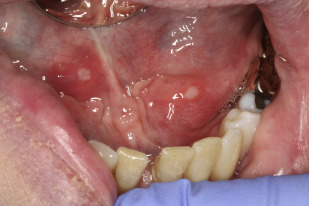

Συμπτώματα της στοματίτιδας από άγχος – Φωτογραφίες

Τα συμπτώματα της στοματίτιδας από άγχος μπορεί να διαφέρουν σε σοβαρότητα και διάρκεια. Τα πιο κοινά συμπτώματα περιλαμβάνουν:

- Επώδυνα έλκη ή πληγές: Αυτά μπορεί να εμφανιστούν στη γλώσσα, στα ούλα, στο εσωτερικό των παρειών ή στα χείλη.

- Ερυθρότητα και φλεγμονή: Οι πληγείσες περιοχές συχνά φαίνονται διογκωμένες και ερεθισμένες.

- Λευκές ή κίτρινες κηλίδες: Αυτές μπορεί να εμφανιστούν στις πληγές, υποδεικνύοντας βακτηριακή ή μυκητιακή λοίμωξη.